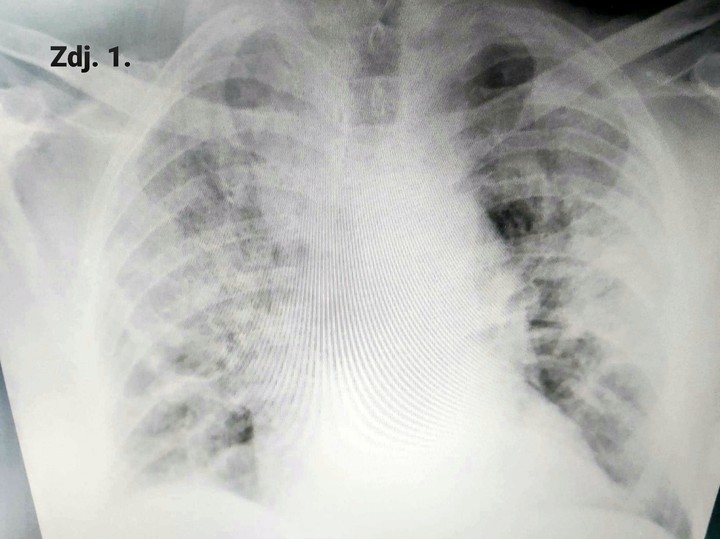

To może przypadek młodego antycovidowca, który trafił do szpitala mniej więcej po tygodniu od wystąpienia objawów. Miał 25 lat, nie był obciążany, żadnymi chorobami, o których by wiedział, co nie znaczy, że nie miał jakichś genetycznych uwarunkowań. Generalnie na pierwszy rzut oka normalny gość. Oczywiście jak to osoba młoda i zbuntowana bagatelizował pierwsze objawy infekcji, rzucał się w wir spotkań towarzyskich, głośno mówiąc, że nie wolno dać się zamknąć „plandemii”. Żył chwilą, ale chwilę potem, kiedy dziwne wrażenie w piersiach zaczęło się nasilać, a dreszczyk emocji wynikający z bycia „rebelem” zniknął, z tyłu głowy pojawiła się u niego obawa. To co najpierw było małym kamyczkiem na klatce piersiowej, stopniowo stawało się wielkim głazem, który leżał na piersiach i nie pozwalał oddychać. Tak działa koronawirus, kradnie nam powietrze, dosłownie kradnie, bo efektywna powierzchnia wymiany gazowej w płucach stopniowo się zmniejsza. Miąższ płuc zalewa mieszanina komórek zapalnych i wysiękającego płynu pozakomórkowego, naszpikowanego szeregiem substancji, tzw. cytokin, które dodatkowo przyprawiają szalejący stan zapalny. Obrazowo można przyrównać płuca do gotującej się zupy. I taki obraz rozhukanego stanu zapalnego obserwujemy na zdjęciach rentgenowskich oraz obrazach tomografii komputerowej, fachowo nazywamy go mleczną szybą. Dla przykładu, na zdj. nr 2 widać obraz prawidłowych płuc. Wszystkie czarne przestrzenie to upowietrzniona, zdrowa tkanka płucna. Promieniowanie X przechodzi przez powietrze bez oporu, nie jest pochłaniane, natomiast każda przeszkoda na jego drodze, czyli te wszystkie komórki zatopione w płynie zapalnym, w pewnym stopniu je pochłaniają, rzucając swoisty cień na obraz zdrowych płuc. Możemy to obserwować jako jasne przebarwienia, które do złudzenia przypominają mleczne, jakby oszronione szkło. Zagranicą stosuje się określenie „frosty glass” i bardzo dobrze widać je na zdjęciu nr 1. Żeby ocenić, ile procent miąższu płucnego jest zajętych zmianami zapalnymi, musimy skorzystać z obrazowania wielopłaszczyznowego, czyli

Zdjęcie nr 2

Na zdjęciu nr 3 a i b widzimy przekrój przez klatkę piersiową, uzyskany za pomocą tej metody obrazowania. Zdjęcia pokazują zakres zmian śródmiąższowych, czyli te wszystkie białe jakby rozlane plamy u jednego pacjenta. Oceniamy je na różnych wysokościach płuc, tutaj na zdjęciu 3a na wysokości szczytów płuc (tuż poniżej ramion) i na poziomie serca (zdj. 3b). Procentowa zawartość zdrowego (czarnego) miąższu jest niewielka. Oczywiście w większości przypadków zmiany w toku leczenia zmniejszają się, a obraz płuc ulega uporządkowaniu, ale ten proces wymaga czasu. Ile? Na tą chwilę, nie mamy jeszcze długoterminowych, opartych na dużej liczbie przypadków badań, które pokazałyby, jak długo i w jakim stopniu organizm będzie wracał do pierwotnego stanu i czy w ogóle wróci.